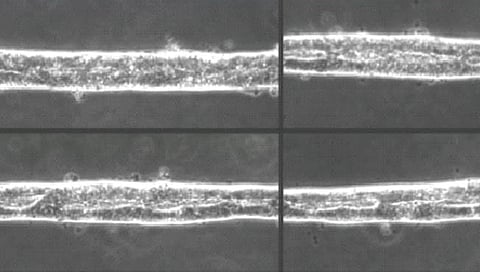

तेल अवीव : संशोधकांनी अनेक मानवी अवयवांसारखे कृत्रिम अवयवही प्रयोगशाळेत विकसित करण्यात यश मिळवलेले आहे. आता प्रथमच मानवी मध्यवर्ती चेतासंस्थेच्या सुरुवातीच्या टप्प्यांचे सूक्ष्म, थ्रीडी मॉडेलही बनवण्यात आले आहे. हे नवे मॉडेल म्हणजे 'ऑर्गनॉईड'चाच एक प्रकार आहे. जिवंत ऊतींचा वापर करून हे सूक्ष्म, थ्रीडी मॉडेल बनवले आहे. ते अकरा आठवड्यांच्या एखाद्या भ्रुणाच्या मेंदूची नक्कल करणारे आहे. चाळीस दिवसांच्या काळात हा कृत्रिम मेंदू प्रयोगशाळेत विकसित करण्यात आला.

त्यामध्ये सूक्ष्म अशा धडकणार्या हृदयापासून ते सूक्ष्म वृषणापर्यंतच्या अनेक अवयवांचा समावेश आहे. यापूर्वीही ब्रेन ऑर्गनॉईड्स बनवण्यात आलेले आहेत. मात्र, यावेळी प्रथमच भ्रुणीय मेंदूच्या सर्व तीन भागांची तसेच मणक्याची नक्कल प्रयोगशाळेत करण्यात आली. याबाबतच्या संशोधनाची माहिती 'नेचर' या नियतकालिकात देण्यात आली आहे. इस्रायलमधील विझमन इन्स्टिट्यूट ऑफ सायन्समधील न्युरोकेमिस्ट्रीचे प्राध्यापक आणि या संशोधनाचे प्रमुख ओर्ली रेनर यांनी याबाबतची माहिती दिली.

हे मेंदूचे मॉडेल अगदी खर्या मेंदूप्रमाणेच कार्य करते, असे त्यांनी सांगितले. त्याचा विकास मानवातील प्लुरीपोटेंट स्टेम सेल्स म्हणजेच मूळपेशींचा वापर करून करण्यात आला. मूळपेशी या शरीरातील अशा पेशी असतात ज्यांचे रूपांतर शरीरातील कोणत्याही अवयवांच्या पेशींमध्ये करता येते.